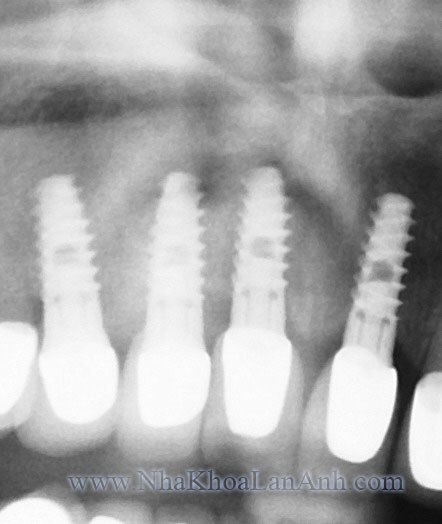

Hệ thống X.Quang Toàn cảnh Kỹ thuật số chuẩn quốc tế

Răng gồm 2 phần: thân răng nhô lên khỏi xương hàm mà ta có thể thấy được, phần còn lại là chân răng nằm trong xương hàm chỉ có thể quan sát nhờ X quang.